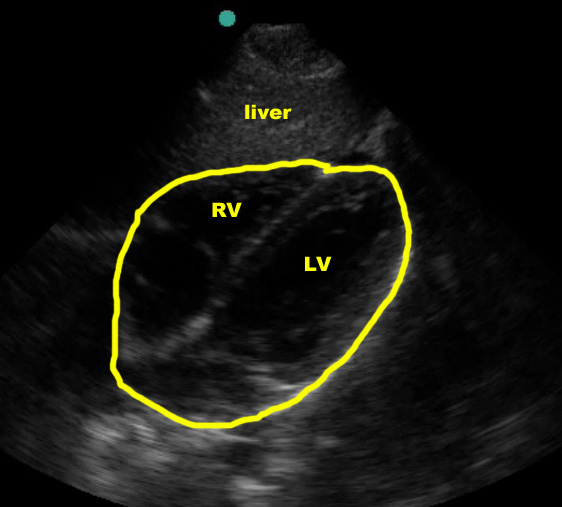

Subxiphoid view

In the normal subxiphoid view (also known as “subcostal”), a small amount of liver should be seen at the top of the screen, superficial to the right ventricle, with the thicker-walled left ventricle deeper. The right ventricle is somewhat V-shaped whereas the left ventricle is more U-shaped. Using typical emergency medicine conventions (marker dot upper left of screen), the atria will be to the left and the apex to the right on the US screen. The entire heart should be surrounded by an echogenic layer of pericardium.

(Figure 10A/11.1)